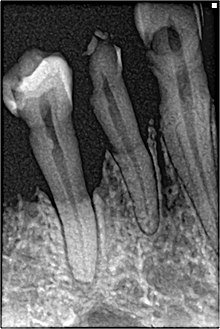

Perhaps the most serious oral condition that can arise is that of oral cancer. However, smoking also increases the risk for various other oral diseases, some almost completely exclusive to tobacco users. The National Institutes of Health, through the National Cancer Institute, determined in 1998 that "cigar smoking causes a variety of cancers including cancers of the oral cavity (lip, tongue, mouth, throat), esophagus, larynx, and lung."[90] Pipe smoking involves significant health risks,[98][99] particularly oral cancer.[100] Roughly half of periodontitis or inflammation around the teeth cases are attributed to current or former smoking. Smokeless tobacco causes gingival recession and white mucosal lesions. Up to 90% of periodontitis patients who are not helped by common modes of treatment are smokers. Smokers have significantly greater loss of bone height than nonsmokers, and the trend can be extended to pipe smokers to have more bone loss than nonsmokers.[101]

Smoking has been proven to be an important factor in the staining of teeth.[102][103] Halitosis or bad breath is common among tobacco smokers.[104] Tooth loss has been shown to be 2[105] to 3 times[106] higher in smokers than in non-smokers.[107] In addition, complications may further include leukoplakia, the adherent white plaques or patches on the mucous membranes of the oral cavity, including the tongue.[108]